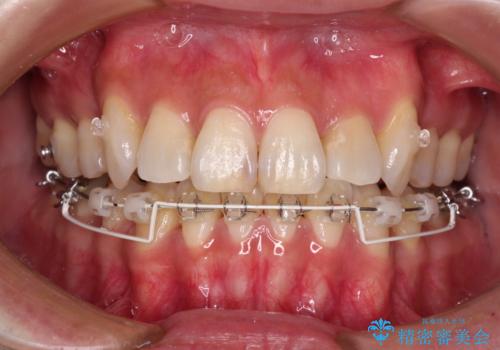

- ハーフリンガル

目立たない装置を希望されたので、上顎が裏側装置のハーフリンガルを選択し、上下左右の小臼歯(計4歯)を抜歯して矯正治療を行うこととしました。

補助装置を併用することで、八重歯を速やかに改善し、治療期間の短縮を図ることとしました。